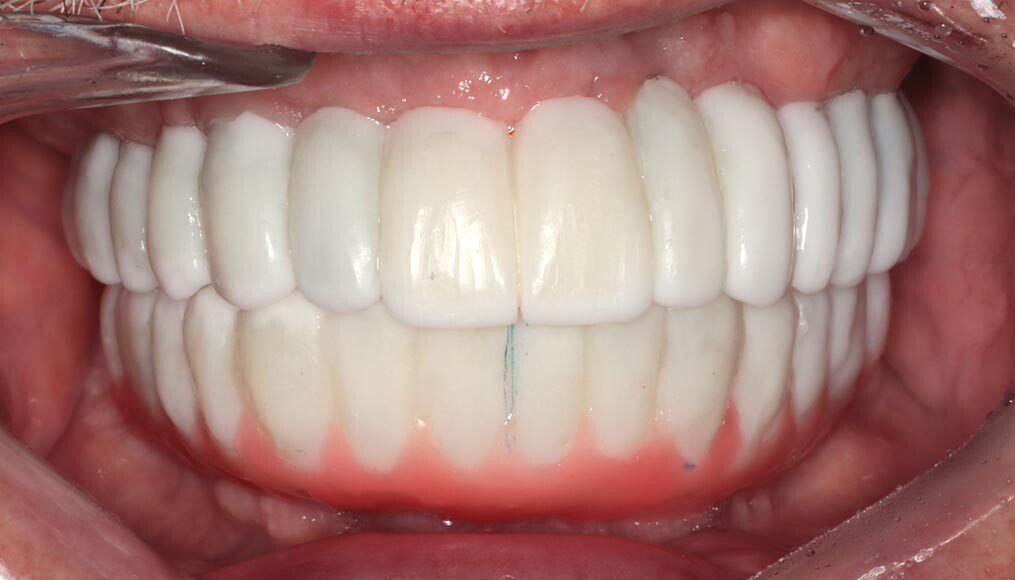

Frontal temporary smile. The patient heals for two additional months and returns to start the process for fabrication of the permanent implant bridges. We begin by assessing and photographing the temporary bridges. There are several issues with the first temporary bridges. Mainly, because he wore his original denture after the first surgery, we were unable to correct the left-to-right cant (slant) until now.

Prototype try-in, smile. The temporary bridges are removed and the prototypes placed. This is where the most scrutiny takes place as we want the patient and family to be thrilled with the appearance and bite. This is the last time changes can be made.